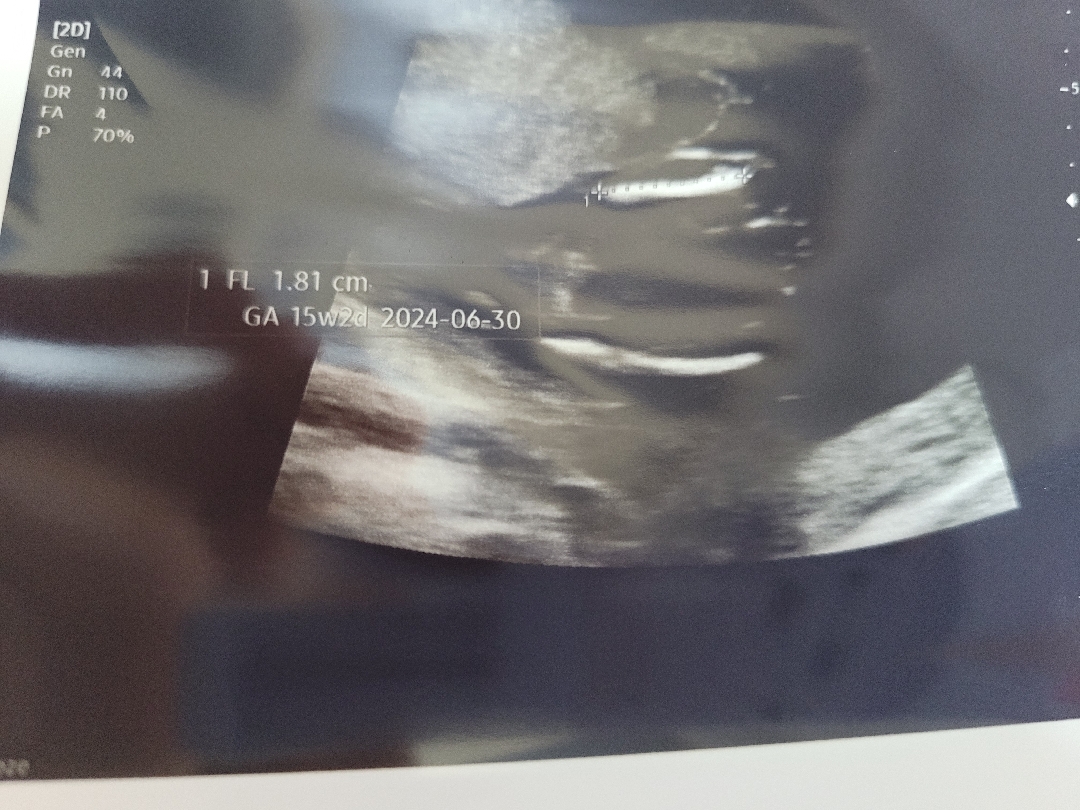

16주 딸 확률 크다는데요.. 왜 제눈에는 뭐가 보이죠?? 배초음파 다리사이 사진 올립니다 다른분들 의견 주시면 감사하겠습니다!!새해복 많이받으세용